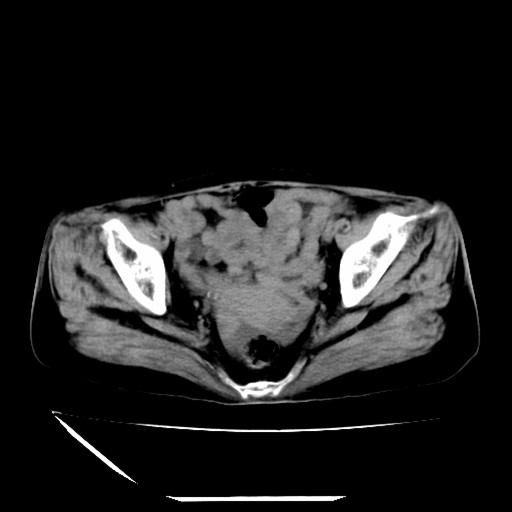

标题: CT16840:女-63岁,下腹部疼痛, [打印本页]

标题: CT16840:女-63岁,下腹部疼痛,

补充资料:血象是13.5,临床拟诊阑尾炎

本人诊断是右肾周围炎,阑尾炎,盆腔少许积液!

诊断右肾周围炎是因为我图像没有发完,诊断阑尾炎是因为相当于阑尾区连续两个层面可以看到增粗的阑尾显影。

支持阑尾炎!局部腹膜增厚,脂肪密度增高。应该手术治疗。